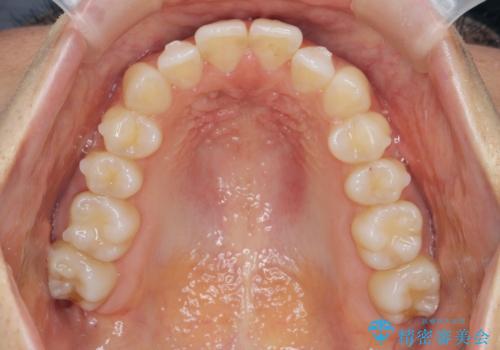

前歯のガタつきをマウスピースで治したい!

- 気になる前歯のガタつきをマウスピースで治療したいと希望され来院されました。

当日に矯正検査を行い、骨格・歯に問題がないことを確認しマウスピースによる矯正治療を進めます。

IPRを前歯部に少量行うことで、非抜歯でも前歯が外に飛び出さない仕上がりを達成できました。